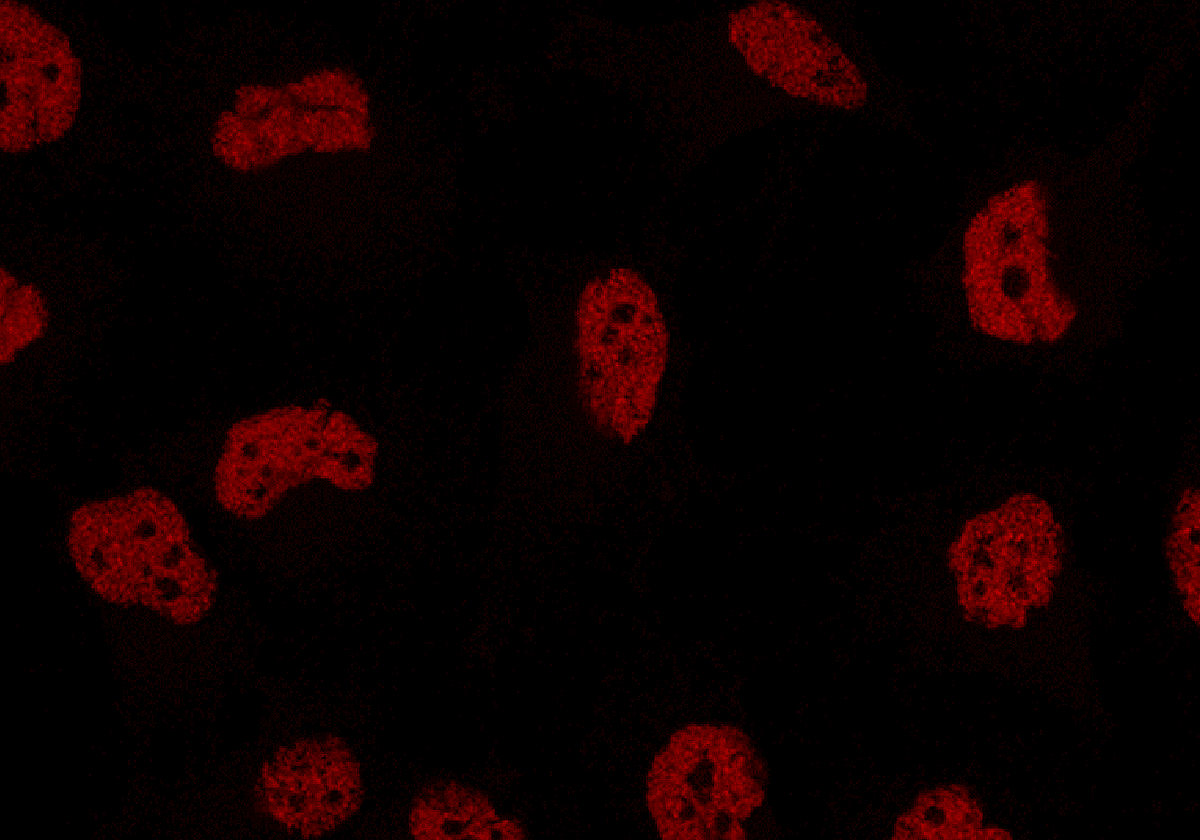

Iniciar sesiónCientíficos de la Universidad de Carolina del Norte publican en 'Nature' un hallazgo clave que podría transformar la prevención y tratamiento del cáncer de mama. El estudio, dirigido por Gaorav Gupta, revela cómo una vía de señalización esencial para la respuesta inmunológica ... inflamatoria, cGAS-STING, se activa para prevenir la formación de cáncer al detectar daños en el ADN dentro de las células.

Los resultados presentan la «llave« para activar esta vía esencial para la respuesta inmunológica inflamatoria. La investigación destaca cómo la enzima GMP-AMP sintasa cíclica (cGAS) desempeña un papel crucial al detectar daños en el ADN y liberarse de histonas, permitiendo la activación del sistema inmunológico.

La clave para liberar cGAS resultó ser la enzima MRE11, conocida por detectar y reparar daños en el ADN.

La conexión entre MRE11 y cGAS también activa una forma especializada de muerte celular llamada necroptosis, facilitando la eliminación de células precancerosas dañadas antes de convertirse en cáncer.